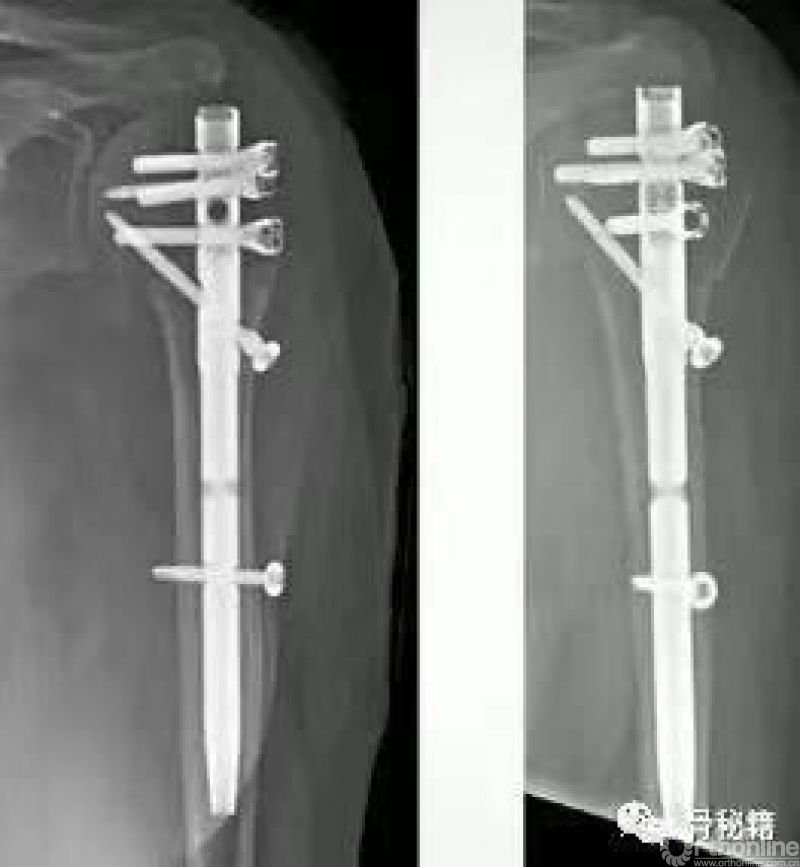

而我们应用髓内钉就是另外一种情况,通过头上较好骨质对主钉的把持来维持整个固定,这个病例为了很好的控制头的固定,使得进针点非常靠内,这样才能把持主头的骨折块,通过主钉来重建生物力学的稳定性,再通过锁定来重建大结节的部位,相对来说失败的几率更小一些

在螺钉的固定方面,Multilock的多平面螺钉与philos的固定已经基本接近了

multilock的螺钉前方是顿头的,不会穿破关节

其后方也有缝线孔,可以结合缝线用来固定肩袖、大结节等组织